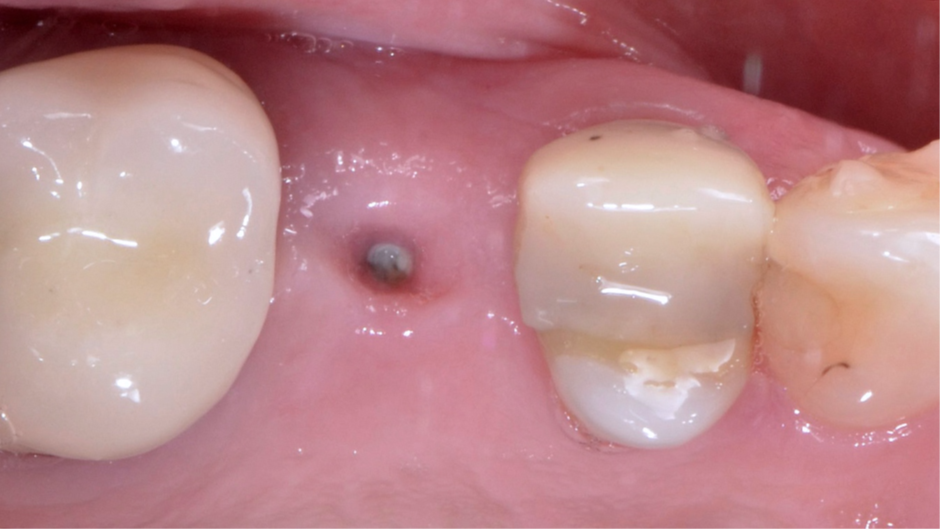

Após a finalização, os dentes adjacentes foram preparados e também receberam coroas provisórias, e a coroa sobre implante provisória foi parafusada no pilar Ideale (Figura 15) usando uma combinação de pressão digital e apertamento do paciente em um rolo de algodão. A isquemia dos tecidos moles peri-implantares pode ser observada, e geralmente desaparece em até 20 minutos. A coroa sobre implante provisória deve ser deixada por um período mínimo de um mês para permitir o adequado condicionamento dos tecidos moles peri-implantares 11,12 (Figura 16). Foi necessário um exame periódico para garantir que a higiene bucal adequada fosse mantida. Após dois meses, quando a mucosa condicionada se estabilizou 13, foi realizado um escaneamento intraoral (Figura 17) para a confecção das coroas definitivas (Figura 18). As coroas definitivas foram fabricadas fresadas em zircônia pura, e após instaladas (Figura 19), o resultado estético e funcional ficou muito favorável (Figura 20).

Figura 19 – Coroas sobre dentes cimentadas e perfil de emergência da coroa sobre implante.

Figura 20 – Coroas definitivas finalizadas: imagem da situação inicial e radiografia periapical de controle imediatamente após a instalação.